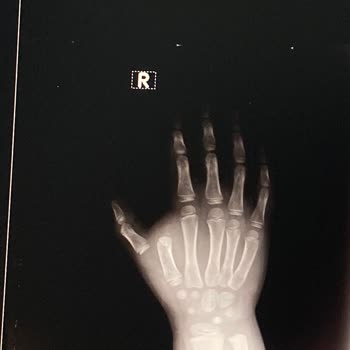

Yanlış Teşhis Ve İlaç Nedeniyle Çocuğumun Sağlığı Tehlikeye Girdi, Mağduriyetim Giderilmedi

20 Ekim 2025 tarihinden bu yana Özel Eryaman Hastanesi Çocuk Sağlığı ve Hastalıkları bölümünde yaşadığımız süreçten dolayı çok mağdur olduk. Genel olarak bölümde yanlış teşhis konuldu ve yanlış ilaç kullanımı önerildi. Bu nedenle çocuğumun iyileşmesi 17 gün gecikti. Resmi dilekçe ile hastaneye başv...